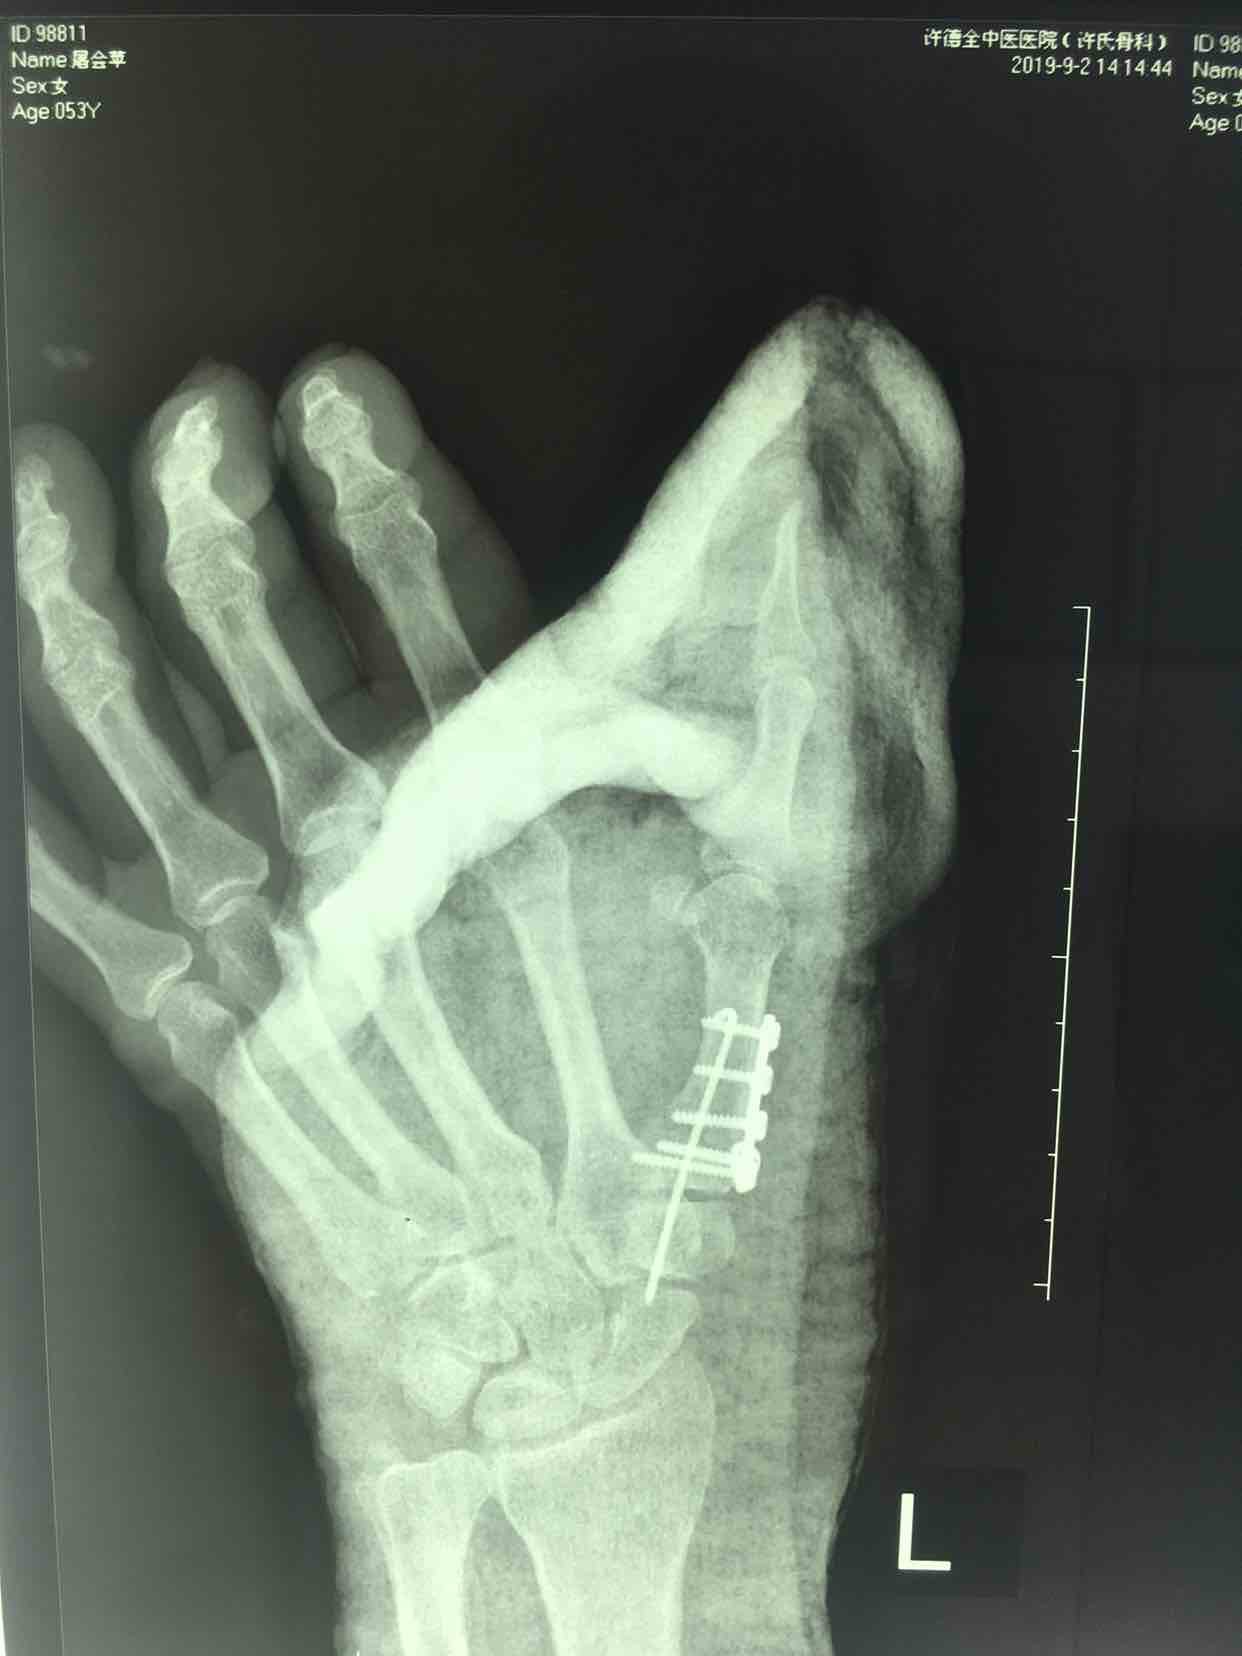

第一掌骨基底部骨折(微钢板固定)

诊断左手第一掌骨基底部骨折在臂丛麻醉下行切复内固定术,术后抗炎消肿等处理,石膏托外固定。